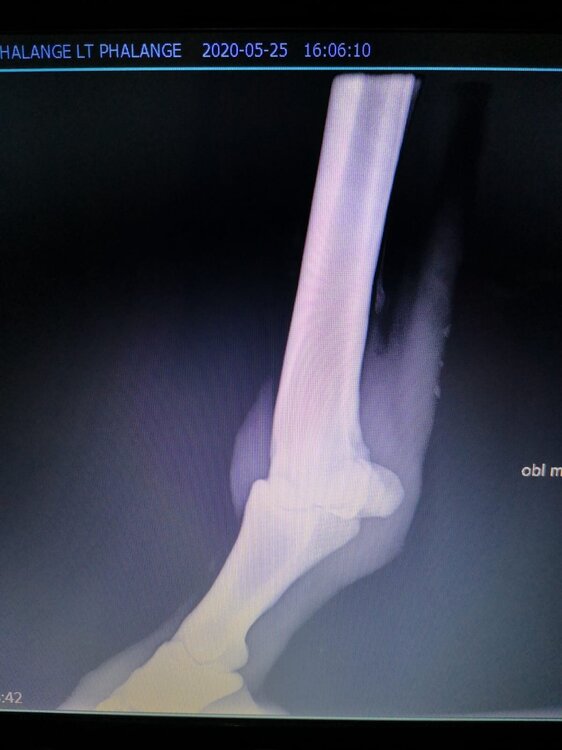

Salve volevo chiedervi qualche informazione in merce tò a un problema che ho avuto con la mia puledra. Qualche settimana fa mentre stavo lavorando alla corda è scivolata urtato l'arto posteriore sinistro. Arrivati in box ho messo dell'acqua a pressione perché si era gonfiato sia il nodello sia il pastorale. Già l'indomani l'arto era sgonfio ritornato normale, quindi ho continuato a lavorarla. Ma dopo qualche giorno di lavoro alla corda leggerissimo, al rientro in box ho notato che sia il nodello che il posturale gonfiavano nuovamente. Allora ho chiamato il veterinario che ha detto che la cavalla aveva una lussazione e mi ha insegnato come cura una fasciatura con della creta per 24h per cinque giorni e un antinfiammatorio. Dopo un paio di giorni la fasciatura ha fatto come delle vesciche e il gonfiore è aumentato dal pastorale alla garra. Abbiamo chiamato un altro veterinario abbiamo fatto vedere anche a lui la cavalla e diceva che poteva essere la frattura del ditino, ma si dovevano fare le lastre per essere sicuri. Ora abbiamo fatto le lastre e il radiologo dice che c'è dell'infiammazione ma non c'è niente di grave. Il veterinario,viste le lastre dice che deve essere operata. Allora abbiamo consultato un'altro veterinario che dice che la cavalla non ha assolutamente niente. Ora io vi allego le radiografie, datemi un vostro parere perché non só più cosa fare. Grazie